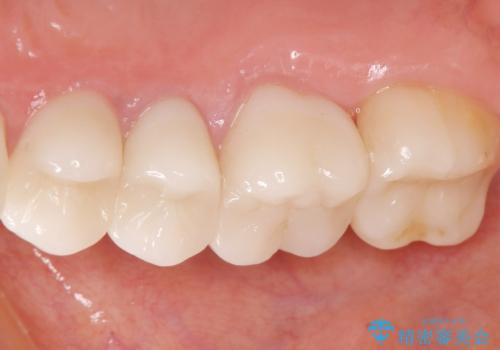

丁寧にう蝕除去と再根管治療を行い症状の改善を確認したのち、セラミッククラウン及びセラミックインレーによる補綴を行いました。

- ¥550,000 (根管治療×1本、土台×1本、クラウン×3本、インレー×1本) ※税込費用は治療当時の料金となります

クラウンの種類:オールセラミッククラウン スタンダード